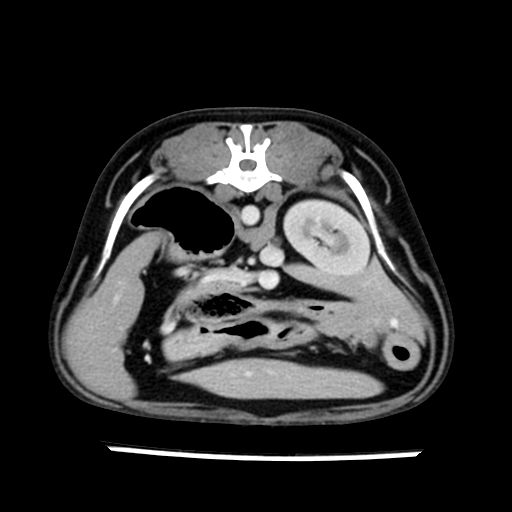

prescritto esame TAC

sequenza immagini limitata al fegato reni e surreni

le immagini ecografiche rispetto alla tac datano circa 7 mesi prima ,le surrenali sono normali nonostante il test acth sia risultato positivo .all’esame TAC dopo diversi mesi risultano aumentate armonicamente nel volume e si individua un forte sospetto di adenoma ipofisario .

sospetto adenoma ipofisario vs. meno probabilmente meningioma della base; intertiziopatia polmonare; lesione espansiva epatica, verosimilmente del lobo laterale sinistro, di sospetta natura neoplastica; lesioni spleniche di natura da definire; iperplasia/ipertrofia delle ghiandole surrenali, bilateralmente; vertebra di transizione del rachide toracico; tenosinovite cronica del muscolo bicipite brachiale di destra.

la tac dopo 7 mesi permette misure tridimensionali 5,2 x 9,2 x 4,5 cm (forma piu’ allungata )